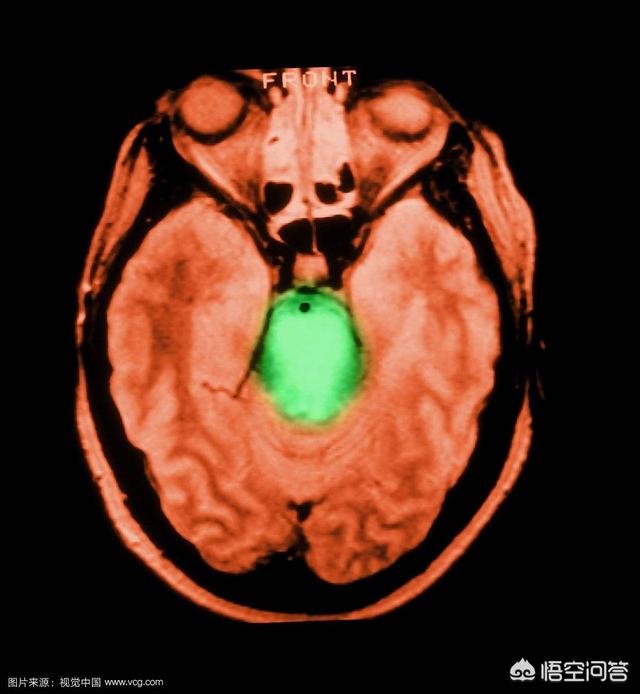

脳梗塞が回復できるかどうかは、脳梗塞の部位と範囲によります。後遺症の原因として多いのは、主に「内果後縁」と呼ばれる場所で、これは手足の活動と同様に片側の顔面筋が支配されるためで、口角が曲がってしまう、片麻痺が起こる、もう一つは「脳幹」です。もう一つは「脳幹」で、その名の通り、木の幹のようなもので、より重要なため、常に脳組織の中心にあり、この場所は機能が密集しており、少し梗塞を起こすと、嚥下障害、片麻痺、複視、斜頸などを引き起こし、重症になると昏睡や植物状態になる。梗塞後、理解できるが話せないものを「運動性失語症」、理解できないが話せるものを「感覚性失語症」と呼ぶ。

赤い線は脳幹の脳橋の位置を示す。